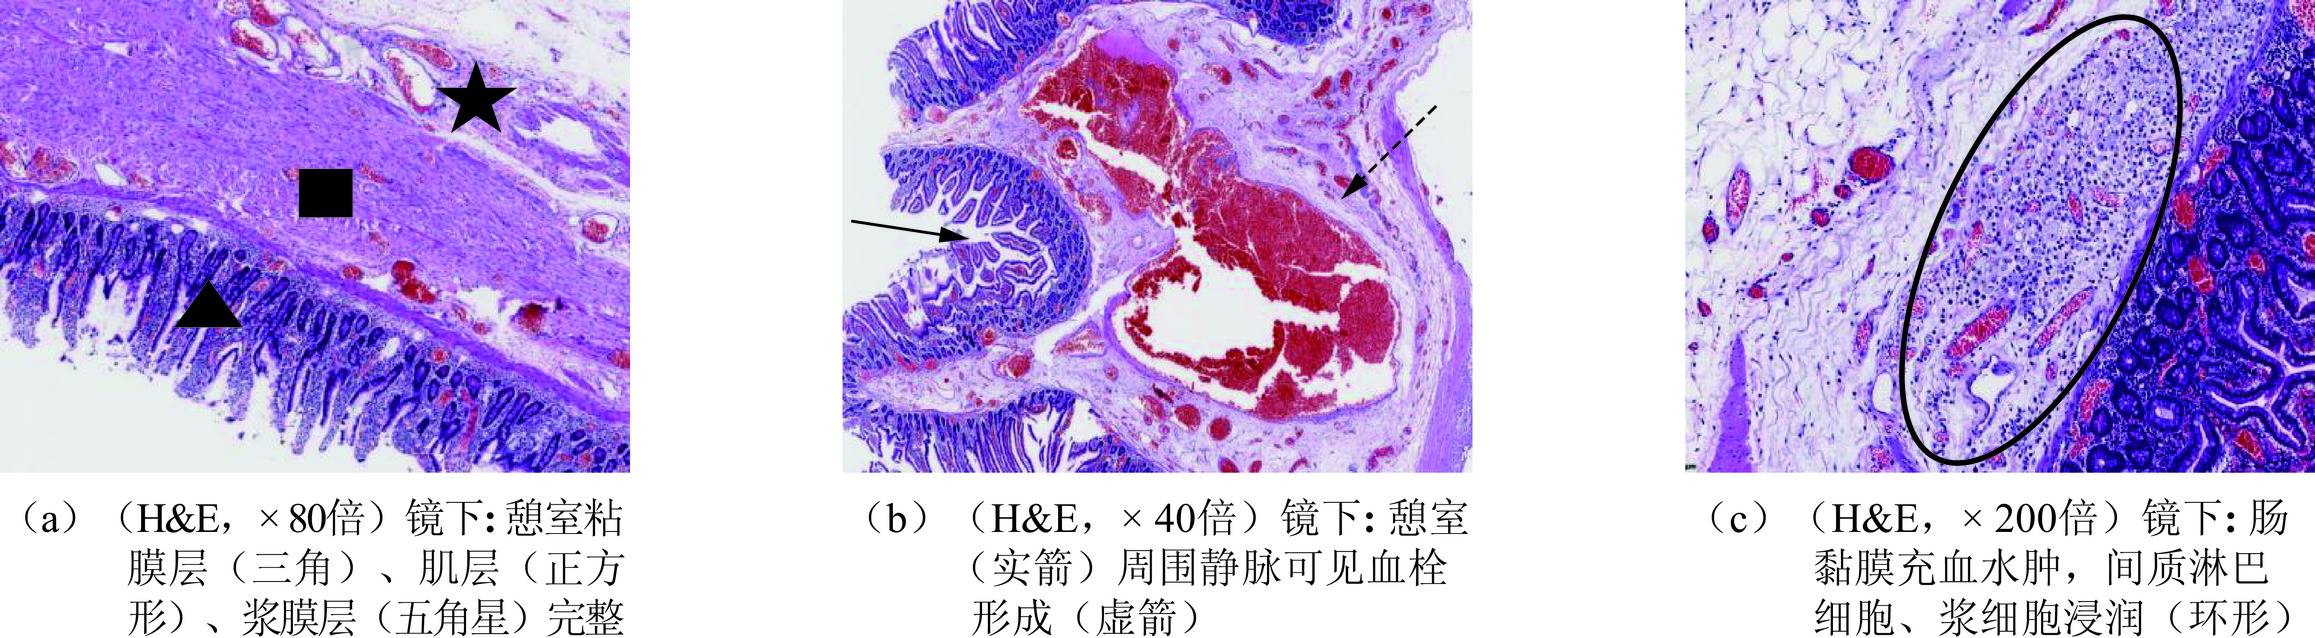

大体病理(图5)所见:空肠上段肠管一段,长约40 cm,直径约3.5 cm,肠壁可见多发类圆形憩室突出肠壁,憩室大小1~3 cm。

显微镜下病理所见,空肠黏膜充血水肿,可见间质淋巴细胞、浆细胞浸润。肠壁见多发憩室,憩室黏膜层、肌层及浆膜层完整,肠系膜上静脉腔内可见血栓(图6)。

空肠憩室主要发生在中老年人,男性发病率高于女性,比例约为2.5∶1[6]。根据憩室壁的结构不同,分为真性憩室和假性憩室,前者是指粘膜、肌层和浆膜均膨出且结构完整,如梅克尔憩室;后者是指只有粘膜和浆膜两层突出,如十二指肠降部憩室、结肠憩室等。本例患者显微镜下可见憩室黏膜层、肌层及浆膜层完整,故为真性憩室。空肠憩室在临床上多无症状,主要影像学特征是空肠壁见向外突出的囊袋状影,其内可见液气平面或筛状低密度影。憩室炎可引起腹痛,而憩室穿孔是憩室炎较为严重的并发症,憩室炎常见原因是憩室出口狭窄,其内容排空困难,引起细菌滋生而导致[7]。